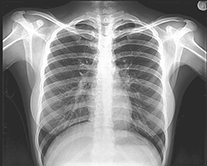

X-ray 진단 또는 X-ray 촬영이란 X선을 인체에 투과시켜 촬영하는 검사를 말한다. 이 방법을 사용하면 조영제나 기구 등을 사용하지 않고 인체의 내부 모습을 판단할 수 있으며, 전후 사진 또는 필요에 따라 측면 또는 대각선 촬영 등을 통해 흔히 가슴 사진, 뼈 사진 등을 얻을 수 있다.

예를 들어 단순 흉부 촬영은 결핵, 폐렴 등의 감염성 폐질환, 폐암 또는 폐전이 등의 종양성 폐질환을 진단하고 추적하는 데 유용한 검사법이며, 단순 복부 촬영은 신장 결석, 장폐색증 등의 진단에, 단순 골격 촬영으로는 팔다리 또는 척추 등의 골절 등을 진단하는 데 매우 유용하다.

촬영되는 주요 부위는 흉부, 복부, 골격, 부비동, 경부 연조직(neck soft tissue) 유방 등이다.

검사방법은 검사 목적에 따라 여러 자세로 촬영을 하게 되는데, 가장 흔히 촬영하는 단순 흉부 촬영의 경우 촬영기를 가슴에 밀착시키고 허리에 손을 올린 자세로 찍는 것을 말하고 필요에 따라 측면 촬영을 할 수도 있다.